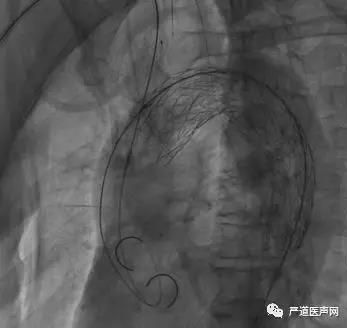

TEVAR+ IA chimney—主动脉覆膜支架与头臂干烟囱支架到位

首先释放胸主动脉覆膜支架(如下图),

然后继续释放头臂干烟囱支架(如下图),